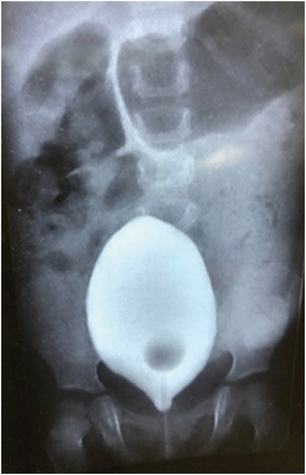

A one-year-old baby presented with chronic constipation and abdominal distension since birth. The child was a full-term baby with a history of delayed passage of meconium. The child also had infrequent episodes of urinary retention. Clinical examination showed a distended abdomen; on the per rectal examination, the rectum was loaded with faeces. Routine laboratory tests and thyroid function tests were normal. On abdomen X-rays, dilated large bowel loops were seen; retrospectively, no mass/opacification was seen on the X-rays. Urological investigations like renal ultrasound and micturating cystourethrogram were normal (Fig. 1).

Fig. 1

Showing the micturating cystourethrography (urinary bladder) good capacity, uniform, no reflux, and dilated bowel loops can be noted.